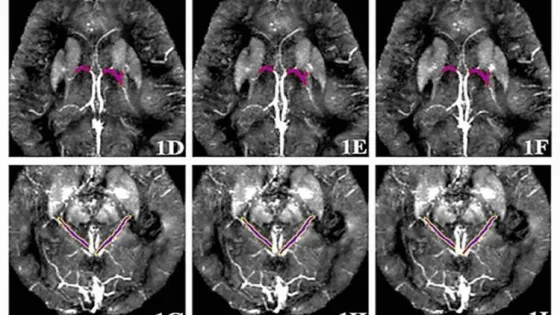

Диагностика включает в себя введение контрастного вещества на основе гадолиния, сканирование головного мозга и измерение магнитной восприимчивости человека в шести мозговых венах. С помощью этих параметров можно получить важную информацию о состоянии кровеносных сосудов и уровнях кислорода, которые могут меняться при развитии болезни Альцгеймера, рассказал пресс-службе Пермского Политеха начальник отдела инноваций ПНИПУ (Пермский Политех) кандидат технических наук Леонид Валерьевич Кожемякин.